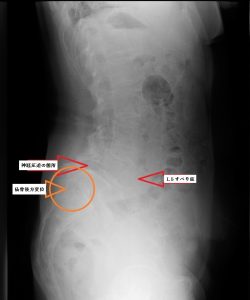

X線検査(レントゲン)では、骨のずれ、腰椎のすべり症などの異常がないか、骨折がないかを調べます。

骨以外にも椎間板が狭くなっていないか、身体の動きによる腰椎の不安定性はないかを確認する必要があります。

また、立位の状態で背骨のずれ、ゆがみ、変形を確認するため、立位全脊椎撮影を行うケースもあります。